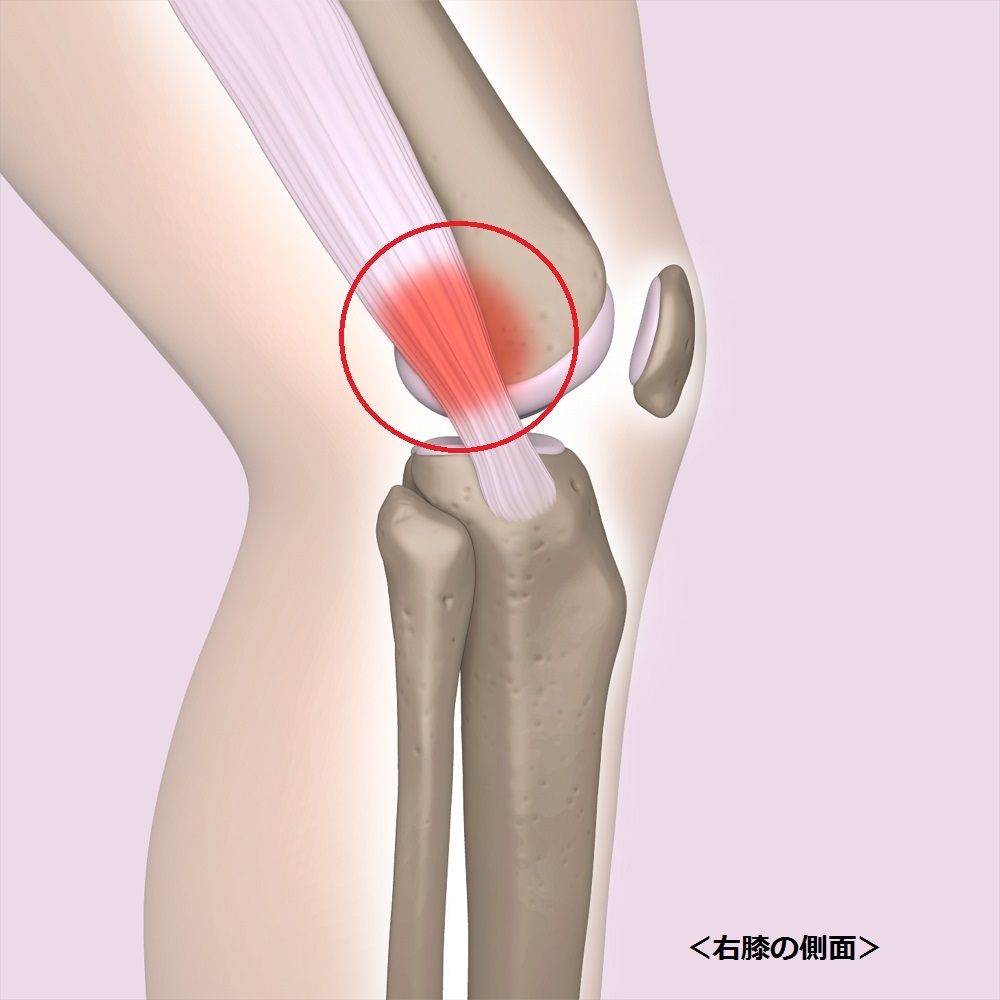

腸脛靭帯炎(ランナー膝)

症状

初期は膝の外側が緊張するような、きしむような違和感や痛みを感じます。ランニング後などに痛みが現れ、休むと治まります。症状が進行してくると、痛みは徐々に大きくなり、なかなか治まらなくなって慢性化します。重症化すると、膝の屈伸が困難となり、膝を伸ばしたまま歩くといった状態になります。